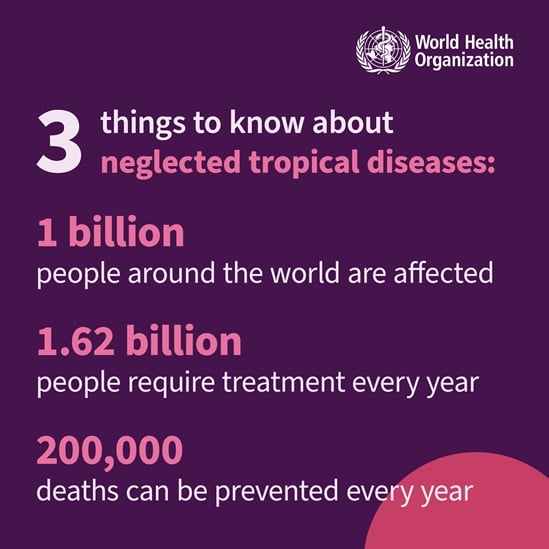

On World Neglected Tropical Disease Day 2024, WHO is calling on everybody, including leaders and communities, to unite and act to address the inequalities that drive neglected tropical diseases (NTDs) and to make bold, sustainable investments to free the estimated 1.62 billion people, in the world’s most vulnerable communities, from a vicious cycle of disease and poverty.

World Neglected Tropical Diseases Day - observed every year on 30 January – aims to spread awareness on the neglected tropical diseases, a diverse group of 21 conditions that are mainly prevalent in tropical areas.